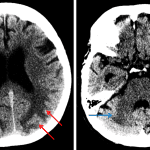

- Multifocal subcortical white matter hypoattenuation, most prominent in the parietal and occipital lobes as well as in the cerebellar hemispheres

- Small focus of hypoattenuation in the left thalamus

- Posterior reversible encephalopathy syndrome (PRES)

Posterior predominant white matter hypoattenuation involving the bilateral parieto-occipital regions and cerebellum in a pattern most suggestive of posterior reversible encephalopathy syndrome (PRES). Recommend brain MRI for further evaluation.

Lacunar infarct versus dilated perivascular space in the left thalamus.

No loss of gray-white differentiation to suggest associated ischemia, though MRI is more sensitive. No acute hemorrhage, mass effect, or hydrocephalus.